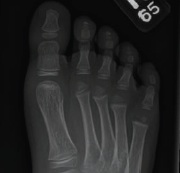

Orthopedics

10/17/2014

Leigh Ann Lather, MD

A previously healthy 5-year-old boy presented for evaluation of an abnormal gait.